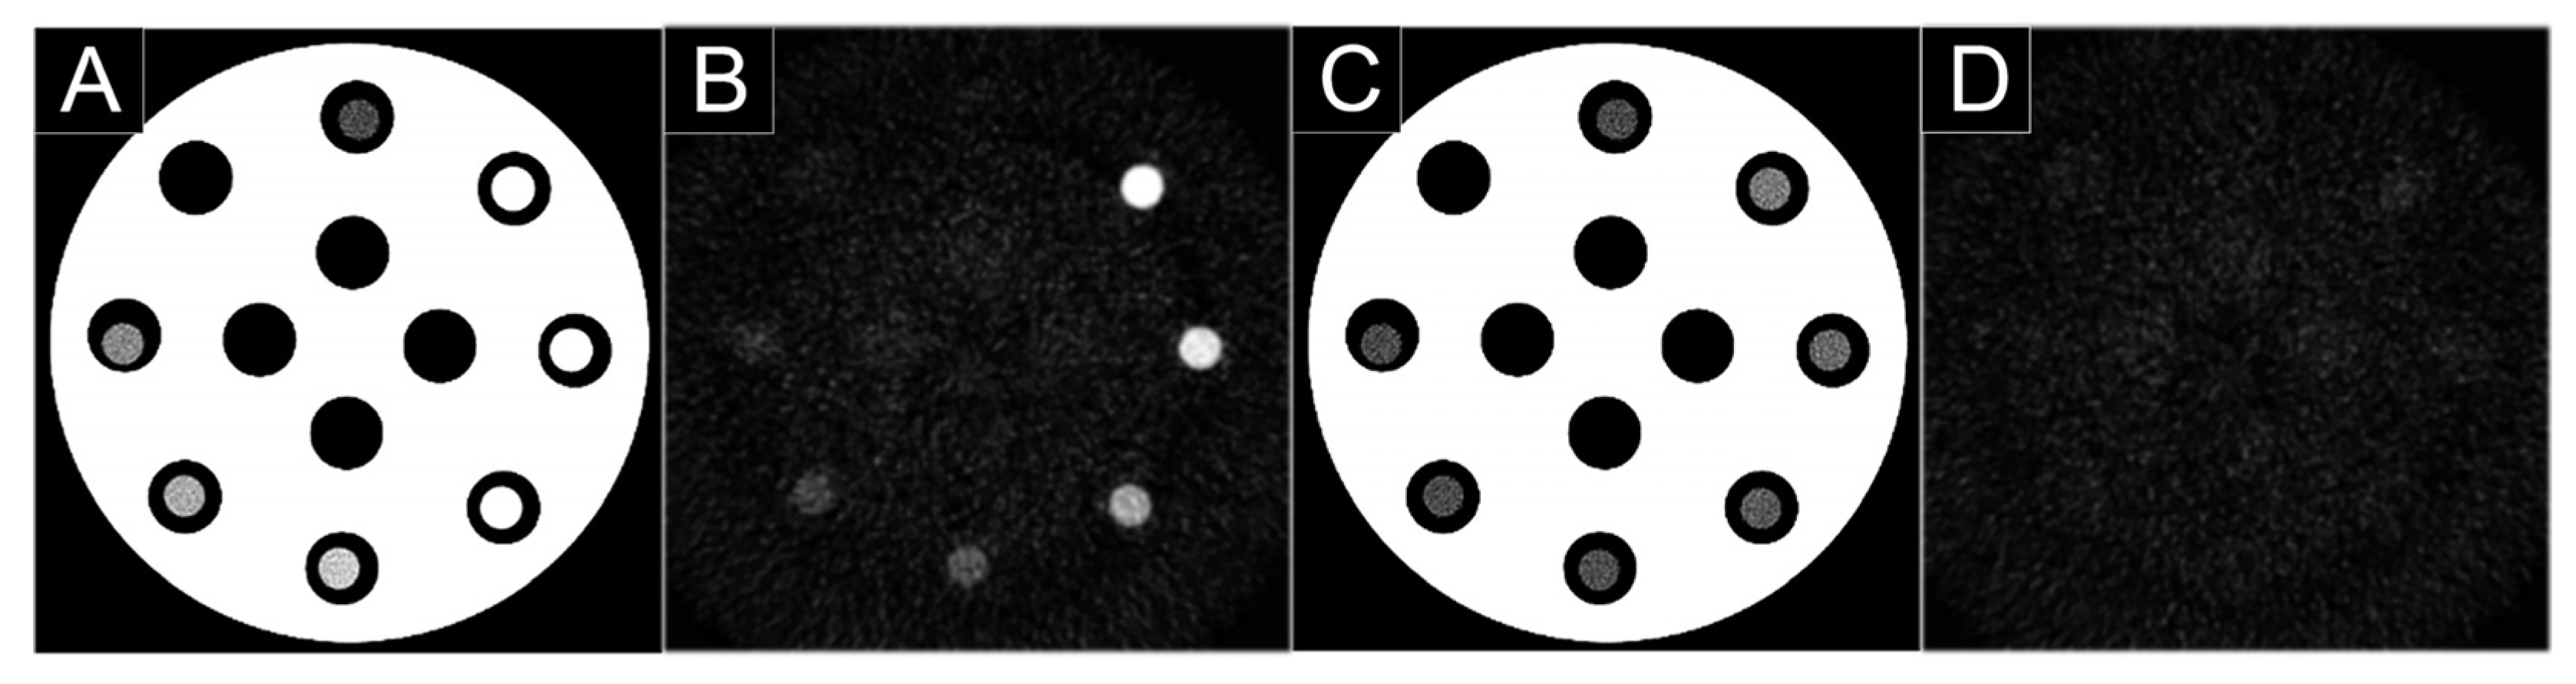

- Si-Mohamed, S.A.; Greffier, J.; Miailhes, J.; Boccalini, S.; Rodesch, P.A.; Vuillod, A.; van der Werf, N.R.; Dabli, D.; Racine, D.; Rotzinger, D.; et al. Comparison of image quality between spectral photon-counting CT and dual-layer CT for the evaluation of lung nodules: A phantom study. Eur. Rad. 2021, in press. [Google Scholar] [CrossRef] [PubMed]

3.2. Nodule Imaging

3.3. Lung Cancer Screening Imaging